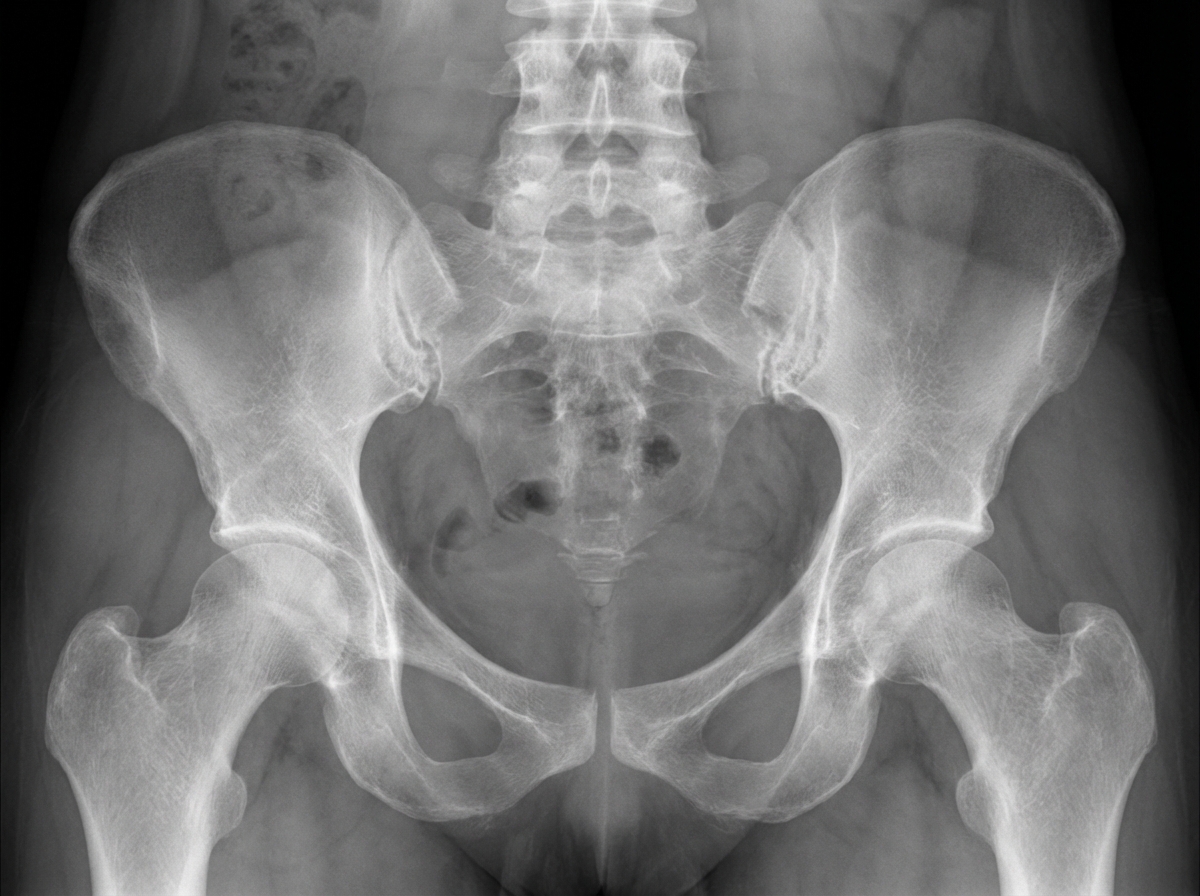

A 32-year-old woman comes to her physician because of increasing back pain for the past 10 months. The pain is worse in the morning when she wakes up and improves with activity. She used to practice yoga, but stopped 5 months ago as bending forward became increasingly difficult. She has also had bilateral hip pain for the past 4 months. She has not had any change in urination. She has celiac disease and eats a gluten-free diet. Her temperature is 37.1°C (98.8°F), pulse is 65/min, respirations are 13/min, and blood pressure is 116/72 mmHg. Examination shows the range of spinal flexion is limited. Flexion, abduction, and external rotation of bilateral hips produces pain. An x-ray of her pelvis is shown. Further evaluation of this patient is likely to show which of the following?